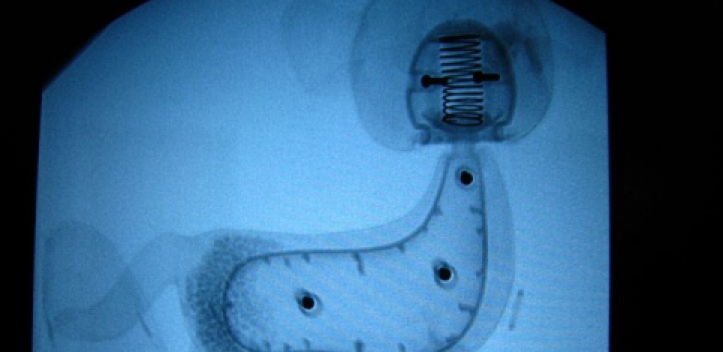

Erstmals in Thüringen haben Kardiologen des Universitätsklinikums Jena bei einem Patienten einen...